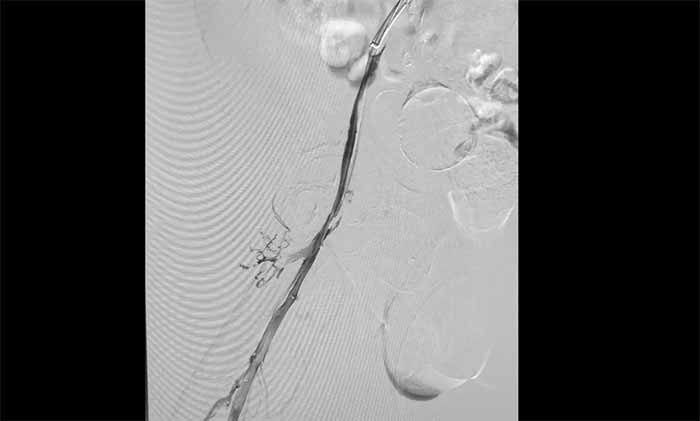

席剛明教授與腦血管病一科4A病區(qū)副主任王貴平博士分析指出,下肢深靜脈血栓一旦脫落,可隨血流引發(fā)肺栓塞,危及生命?紤]到患者血栓形成時(shí)間較長(zhǎng)、抗凝效果不佳,團(tuán)隊(duì)決定行介入手術(shù)治療。術(shù)后造影顯示血栓基本消失,下肢靜脈恢復(fù)通暢,患者右下肢腫脹明顯緩解。

▲ 取出大量血栓